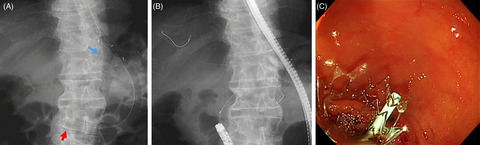

We investigated the efficacy and safety of surgery and external beam radiotherapy (EBRT), in patients with hepatocellular carcinoma (HCC) involving the inferior vena cava (IVC) and/or right atrium (RA) through a comparative meta-analysis. A systematic search of PubMed, MEDLINE, EMBASE, and the Cochrane library was performed for entries until July 2020. Eighteen studies with 22 cohorts were included, encompassing 755 patients. The pooled median overall survival (OS) and 1- and 2-year OS rates were 14.2 months, 55.6%, and 27.4%, respectively. The pooled median OS in the surgery and EBRT arms were 15.3 and 11.7 months, respectively. The pooled 1-year OS rate in the surgery arm was significantly higher than that in the EBRT arm (62.4%, 95% CI: 53.8%-70.3% vs 48.8%, 95% CI: 40.9-56.8, respectively; P = .023), while the 2-year OS rates were similar (27.5%, 95% CI: 19.7%-37.1% vs 26.9%, 95% CI: 20.7-34.2, respectively; P = .913). In the surgical arm, the perioperative mortality and grade ≥3 complication rates were 0%-7.6% and 3.9%-67%, respectively. Grade ≥3 complications and radiation-induced liver disease were rarely observed in the EBRT arm. Surgery could be an effective local modality for achieving the best survival rate, though it requires efforts to minimize morbidities and careful patient selection. EBRT, as a noninvasive modality, is a valid palliative option, especially for high-risk patients with a shorter life expectancy.